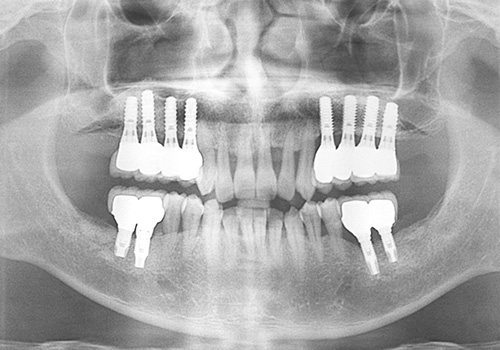

김○근님 임플란트 식립 전

2023년 2월

김○근님 임플란트 식립 후

2023년 6월 -